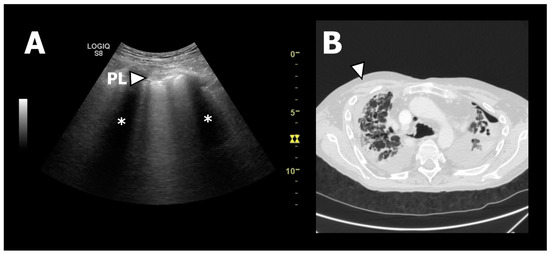

In 2017, Davidsen et al. published a case report proposing that TUS could be used as a novel tool to phenotype CLAD [31]. The same study group further investigated this hypothesis in a later observational study with the prospective inclusion of 25 lung transplant recipients with new-onset CLAD (n(BOS):n(RAS) = 19:6), who were examined with TUS and HRCT, performed within an average time window of ten days prior to or after TUS [12]. HRCT was used as the gold standard for the PPFE findings that would correspond to the TUS findings demonstrating pleural thickening. It was found that the RAS patients were presenting differently from the BOS patients, with a significant difference in pleural thickening, as measured by a TUS of 5.6 mm and 2.9 mm (normal pleura thickness is 1 mm), respectively, and was consistent with a significantly higher prevalence of PPFE findings on HRCT in the RAS compared to BOS patients. Importantly, the study proved a high diagnostic accuracy of TUS to identify apical pleural thickening in either the anterior or posterior apical zones in RAS patients as a surrogate marker of HRCT-verified PPFE in lung transplant recipients (i.e., with a sensitivity of 100% (95% CI; 54–100%), specificity of 100% (95% CI; 82–100%), positive predictive value (PPV) of 100% (95% CI; 54–100%), and a negative predictive value (NPV) of 100% (95% CI; 82–100%)) (Figure 3). Hence, confirmation of this novel so-called RAS-sign in lung transplant recipients with developed CLAD increased the probability of RAS over BOS. As such, it was concluded that TUS could discriminate RAS from BOS and thus be used as an up-front tool for CLAD phenotyping, which clinically impacts the reduction of time for diagnosing RAS, which is crucial since its prognosis is inferior to BOS [32,33,34].

Figure 3.

TUS and HRCT findings from a patient with RAS. (A): The white arrow indicates TUS from zone R1 showing a thickened and fragmented pleural line. * indicates the subpleural “shadowing” corresponding to the ribs. (B): Axial HRCT image of the upper lobes showing fibrotic pleural and septal thickening consistent with PPFE. The white arrow corresponds to TUS zone R1 presented in (A) [12].